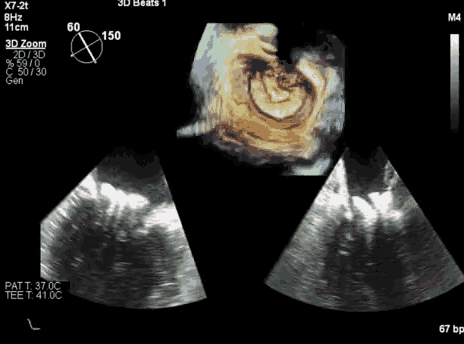

术中食道心超引导人工瓣膜定位释放